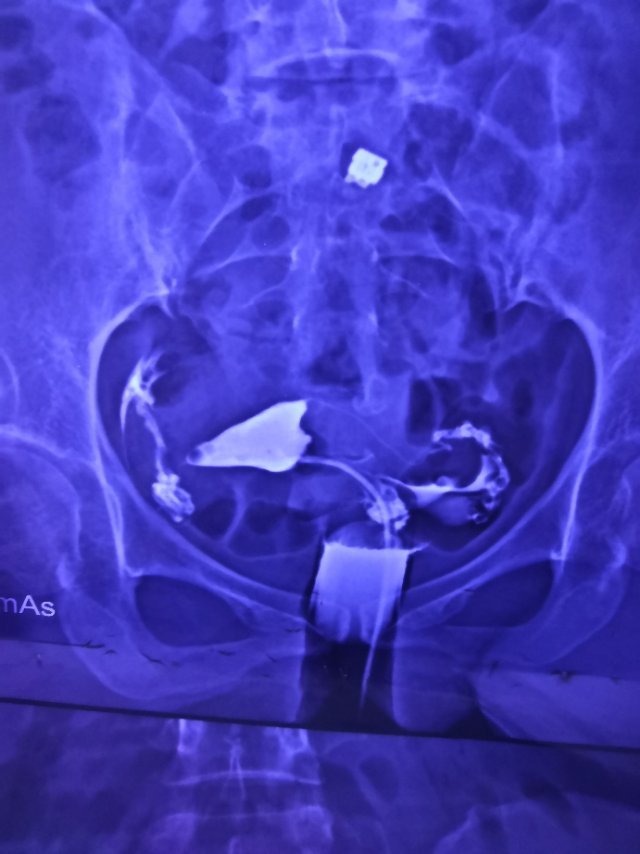

输卵管造影两年前的需要手术吗

这种必须做手术么还是取了胚胎不是非要做

这个手术不是非得要马上做,需要根据你的年龄、生育计划等来综合评估并权衡利弊后再决定是否需要手术以及什么时候做。如果是做试管通常为了避免输卵管积液及炎症因子逆流至宫腔影响胚胎着床等,会行输卵管结扎等手术,这个手术通常在移植前完成